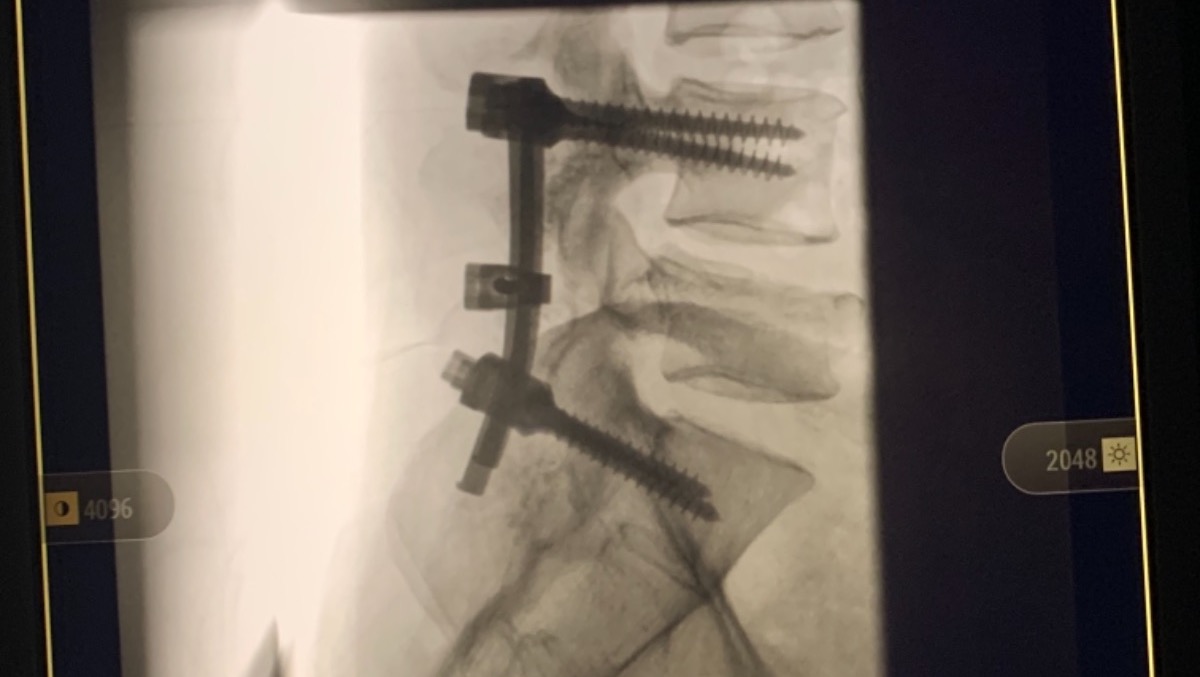

In 2007, I was in a near fatal accident and fell off of a 20 foot bridge. I was rushed to the hospital where they put me in a drug induced coma for two weeks. When I woke up I had an “external fixator” on my right leg and foot with rods and pins sticking out everywhere. My right tibia and fibula were broken and both feet were shattered. My left foot had a steel plate secured with seven screws. My right foot had an “Ex-fix” secured with rods and pins. My left wrist was shattered and required five pins to put back together. My back was broken as well and had to be fused together at L4-S1 with more rods and screws.